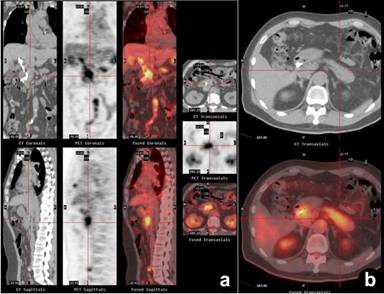

A 52-year-old Chinese male was referred to our center for further workup of acute pancreatitis and common bile duct stricture. His medical problems included asthma, chronic cough, allergic rhinitis, and chronic rhinosinusitis for approximately 20 years; recently, these conditions worsened. At our center, the patient underwent pancreas protocol computed tomography (CT) scan, endoscopic ultrasound (EUS), and endoscopic cholangiopancreatography (ERCP). CT scan of the abdomen was negative for pancreatic lesion. EUS showed one hypoechoic lesion (2.6x1.8 cm) in the head and another hypoechoic lesion (2.2x2.2 cm) in the body of pancreas; (EUS)-guided fine needle aspiration (EUS-FNA) of the two lesions was negative for pancreatic neoplasm. ERCP demonstrated a high grade common bile duct stricture, which was treated with stent placement; common bile duct brushing cytology was also negative for cancer. At this juncture, pancreaticoduodenectomy was contemplated because he may have pancreatic cancer or cholangiocarcinoma despite above negative workup. In the interim, PET/CT was performed. PET/CT revealed diffuse inflammation in the pancreas (Figure 1). Extrapancreatic lesions in the abdominal aorta, hilar region of lungs, salivary glands, and gallbladder were also observed on PET/CT (Figures 2 and 3). Because of these findings, the patient was suspected to have systemic IgG4-related sclerosing disease. As a result, immunoglobulin G (IgG) and IgG4 levels were measured. Only IgG level was elevated (IgG: 2,430 mg/dL, reference range: 767-1,590 mg/dL; IgG4: 41.2 mg/dL, reference range: 2.4-121.0 mg/dL). Immunoglobulin E (IgE) was 527 KU/L (reference range: 0-127.0 KU/L), and the carbohydrate antigen 19-9 (CA 19-9) was 37 U/mL (reference range: 0-37 U/mL). In order to support the suspected diagnosis, CT-guided biopsy of the left submandibular gland was performed and immunochemical staining was consistent with IgG4-related sclerosing disease (more than 30 IgG4-positive cells per high power field). Therefore, he was treated with prednisone 40 mg daily. After one month of corticotherapy, a repeated PET/CT showed resolution (Figure 4); however, there was an increase in IgG4 level (546 mg/dL) with a decrease in IgG (1,310 mg/dL). The patient’s symptoms resolved with steroid and the scheduled pancreaticoduodenectomy was canceled. Subsequently, prednisone was tapered off and azathioprine 175 mg (2 mg/kg) daily was initiated for maintenance therapy. After one year of treatment, he was asymptomatic.

Figure 1. PET/CT composite (a.) and axial PET/CT images (b.) show diffuse tracer uptake by the pancreas (crosshairs). Case#1. |